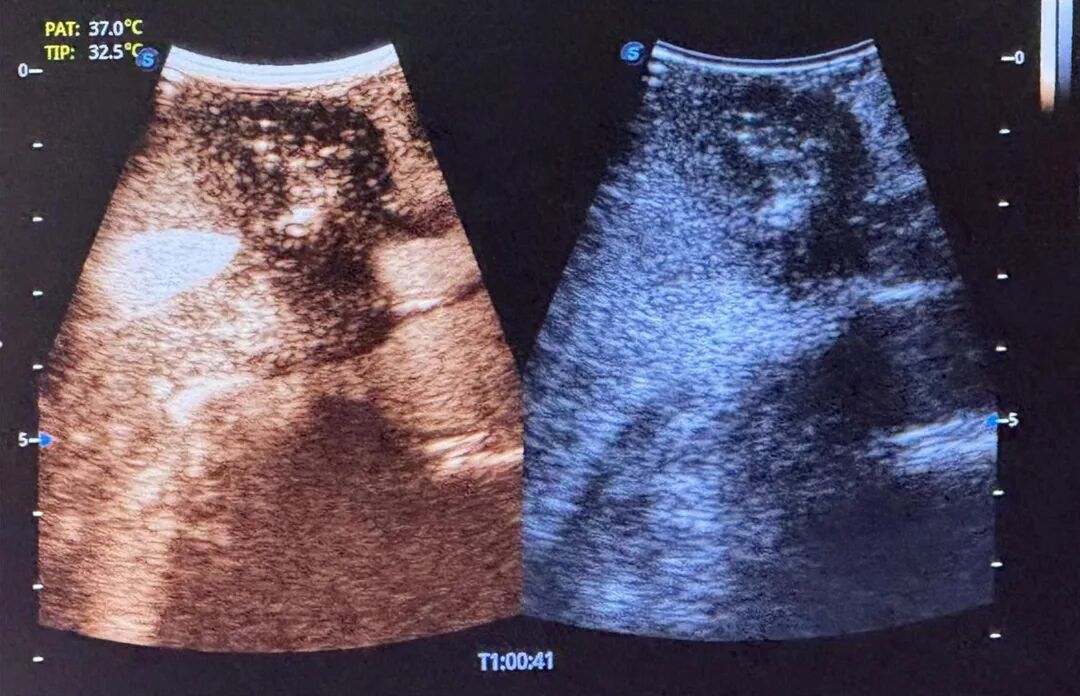

术后超声造影显示肿瘤部位呈无血供现象,周边血管结构保存完整,消融效果良好且安全。消融完成后,术者退出电极针,手术顺利结束,术后给予对症支持治疗,患者恢复良好。

术后即刻造影▲